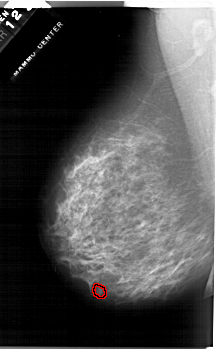

A_1284_1.RIGHT_CC

RIGHT_CC LINES 6571 PIXELS_PER_LINE 3916 BITS_PER_PIXEL 12 RESOLUTION 43.5 NON_OVERLAY

FILE: A_1284_1.LEFT_MLO.OVERLAY

TOTAL_ABNORMALITIES 1

ABNORMALITY 1

LESION_TYPE MASS SHAPE OVAL MARGINS OBSCURED

ASSESSMENT 4

SUBTLETY 3

PATHOLOGY BENIGN

TOTAL_OUTLINES 1

BOUNDARY